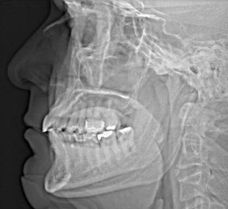

Die normale Röntgenaufnahme hat einen würdigen Nachfolger erhalten. Die 3-D-Diagnostik mittels Digitalen Volumentomographen (DVT) bietet speziell im Bereich des Kopfes bisher unerreichte Möglichkeiten zur Darstellung der Knochen und Zähne. Dadurch wird in der Diagnostik und Therapieplanung eine bislang unerreichte Präzision bei niedrigster Strahlenbelastung erzielt.

Aufgrund der detailgetreuen dreidimensionalen Darstellung von Zähnen und Kieferknochen und durch die geringe Strahlenbelastung steht die 3D Volumentomographie für eine Vielzahl von Indikationsbereichen zur Verfügung, wie zur räumlichen Diagnostik von Wurzelkanälen und parodontalen Strukturen, zur Beurteilung von Nachbarstrukturen, wie Zähne, Implantate, Kieferhöhle und Nerven, zueinander. Dadurch läßt sich eine verbesserte Diagnose- und Planungssicherheit erreichen.

In der Implantologie kann mit Hilfe der exakten 3D Diagnostik das vorhandene Knochenangebot genau auf Qualität und Quantität untersucht werden, wodurch eine optimale Nutzung des Knochens möglich wird. Auch lassen sich sensible anatomische Strukturen, wie Nerven oder Kieferhöhle genau erfassen, wodurch in Verbindung mit dreidimensionaler Planung die Sicherheit für den Patienten erhöht wird.